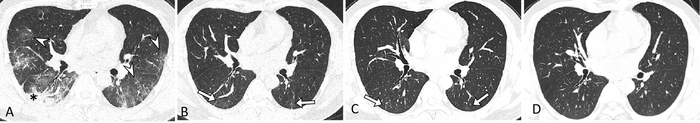

OAK BROOK, Ill. – Chest CT revealed persistent lung abnormalities in patients two years after COVID-19, according to a study published in Radiology , a journal of the Radiological Society of North America ( RSNA ). This is the first research paper with two-year follow-up data on COVID-19 lung effects.

Residual lung abnormalities after discharge from the hospital included fibrosis (scarring), thickening, honeycombing, cystic changes, dilation of the bronchi, and more.

Over two years, the incidence of lung abnormalities gradually decreased. At six months, 54% of patients showed lung abnormalities. On two-year follow-up CT scans, 39% (56/144) of the patients had lung abnormalities, including 23% (33/144) with fibrotic lung abnormalities and 16% (23/144) with non-fibrotic lung abnormalities.

“In particular, the proportion of fibrotic interstitial lung abnormalities, an important precursor to idiopathic pulmonary fibrosis, remained stable throughout follow-up,” the authors said. “Therefore, the fibrotic abnormalities observed in our study might represent a stable, irreversible pulmonary condition, such as lung fibrosis, after COVID-19.”